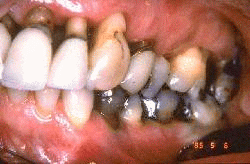

Mujer de 68 años de edad tratada por enfermedad periodontal por medio no quirúrgico (raspado y alisado radicular) seis años antes. El margen  gingival se ha retraído entre 3-5 mm y las profundidades de los surcos al sondaje es de  2 - 3 mm. Ella demuestra una higiene oral excelente y la progresión de la  enfermedad periodontal se ha detenido. Se observa signos de abrasión dental por el cepillado en los incisivos.

Mujer de 68 años de edad  que fue tratada por medio de tratamiento no quirúrgico (raspado y alisado radicular) hace ocho años. El margen  gingival se ha retraído entre 3-5 mm. Las profundidades de los surcos gingivales son 2-3 mm. Ella demuestra una higiene oral excelente y la progresión de enfermedad periodontal se ha detenido. Se observa evidencia de abrasión por el cepilldo dental. a lo largo del margen gingival.